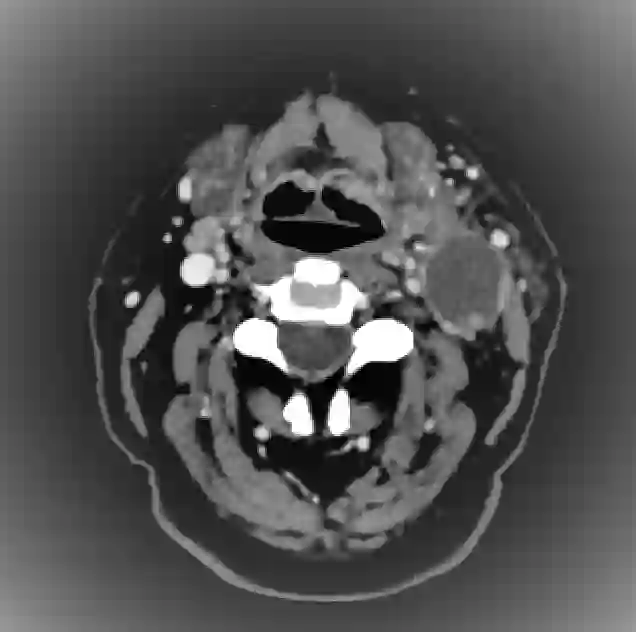

Organ at risk (OAR) segmentation is a critical process in radiotherapy treatment planning such as head and neck tumors. Nevertheless, in clinical practice, radiation oncologists predominantly perform OAR segmentations manually on CT scans. This manual process is highly time-consuming and expensive, limiting the number of patients who can receive timely radiotherapy. Additionally, CT scans offer lower soft-tissue contrast compared to MRI. Despite MRI providing superior soft-tissue visualization, its time-consuming nature makes it infeasible for real-time treatment planning. To address these challenges, we propose a method called SegReg, which utilizes Elastic Symmetric Normalization for registering MRI to perform OAR segmentation. SegReg outperforms the CT-only baseline by 16.78% in mDSC and 18.77% in mIoU, showing that it effectively combines the geometric accuracy of CT with the superior soft-tissue contrast of MRI, making accurate automated OAR segmentation for clinical practice become possible. See project website https://steve-zeyu-zhang.github.io/SegReg